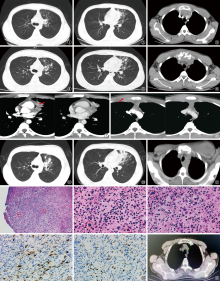

An examination of the clinical diagnostic and therapeutic procedures in a case of classic Hodgkin lymphoma, initially presenting with pulmonary infiltration, sternal bone destruction, and abscess formation

Classical Hodgkin lymphoma (CHL) accompanied by bone destruction and abscess formation is clinically rare and easily misdiagnosed as an infectious disease. This article reports a case of CHL in a young male patient presenting primarily with pulmonary infiltration, sternal destruction, and abscess formation, aiming to explore its clinical features and diagnostic approach to reduce misdiagnosis. The patient was a young male who initially presented with cough and chest pain. Imaging findings suggested left upper lung infiltration, sternal bone destruction, mediastinal mass, and possible left anterior chest wall abscess. Multiple etiological examinations failed to confirm an infectious origin, and both anti-infective therapy and diagnostic anti-tuberculosis treatment showed poor efficacy. The diagnosis was ultimately confirmed by pathological examination of a left supraclavicular lymph node biopsy as CHL (immunohistochemistry: CD30 positive, CD15 positive, PAX5 weakly positive). After standardized treatment, the lesions completely resolved. This case suggests that lymphoma should be considered in patients with bone destruction and abscess formation who present with suspected infection but lack etiological evidence and respond poorly to treatment.